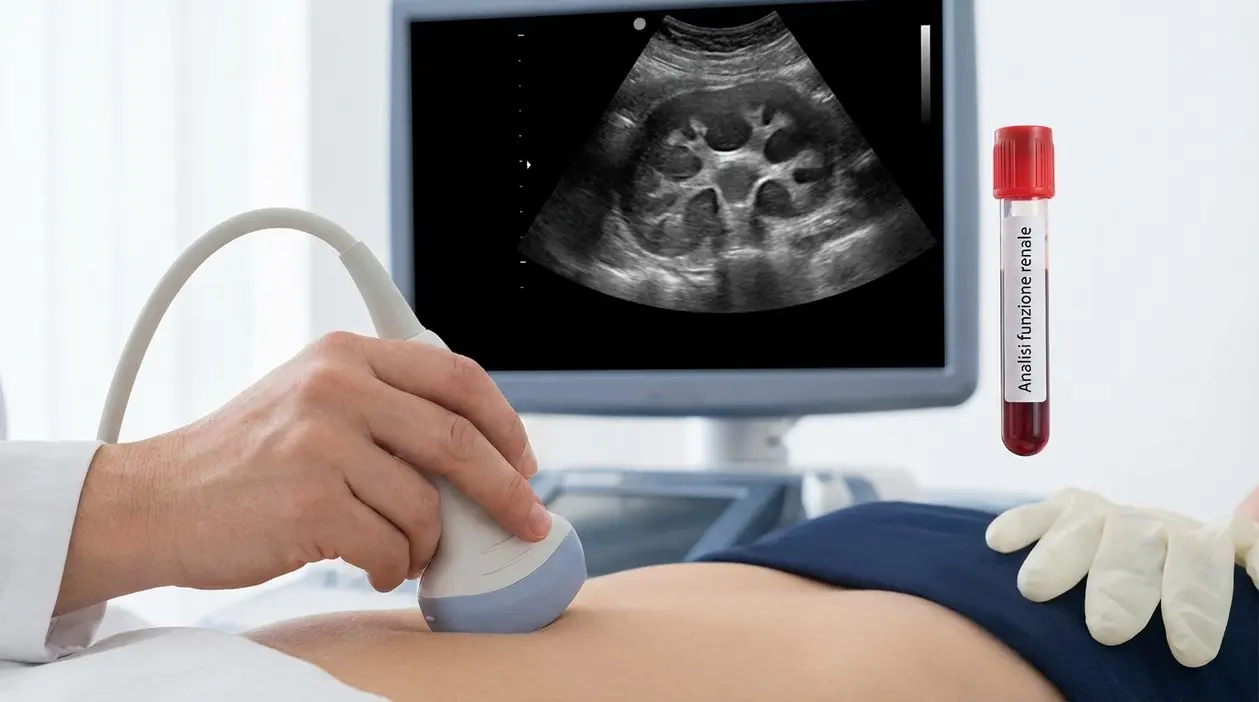

L’esame di primo livello: l’ecografia

Il primo passo, quasi sempre, è la ecografia renale o addominale. È un esame non invasivo, rapido e privo di radiazioni, molto utile per confermare la presenza di una dilatazione delle vie urinarie.

L’ecografia può mostrare:

- se uno o entrambi i reni sono dilatati

- il grado della dilatazione

- eventuali segni indiretti di ostruzione

- qualche possibile causa, come calcoli più evidenti o alterazioni della vescica

Il suo limite è altrettanto importante: spesso dice che l’idronefrosi c’è, ma non basta da sola a spiegare l’origine del problema. Ed è qui che entrano gli esami di secondo livello.

Gli esami del sangue e delle urine contano molto

Accanto alle immagini, servono quasi sempre anche gli esami di laboratorio. Le urine possono mostrare infezione, ematuria o cristalli compatibili con calcolosi. Gli esami del sangue, come creatinina, azotemia ed eGFR, aiutano a capire se il rene sta soffrendo.